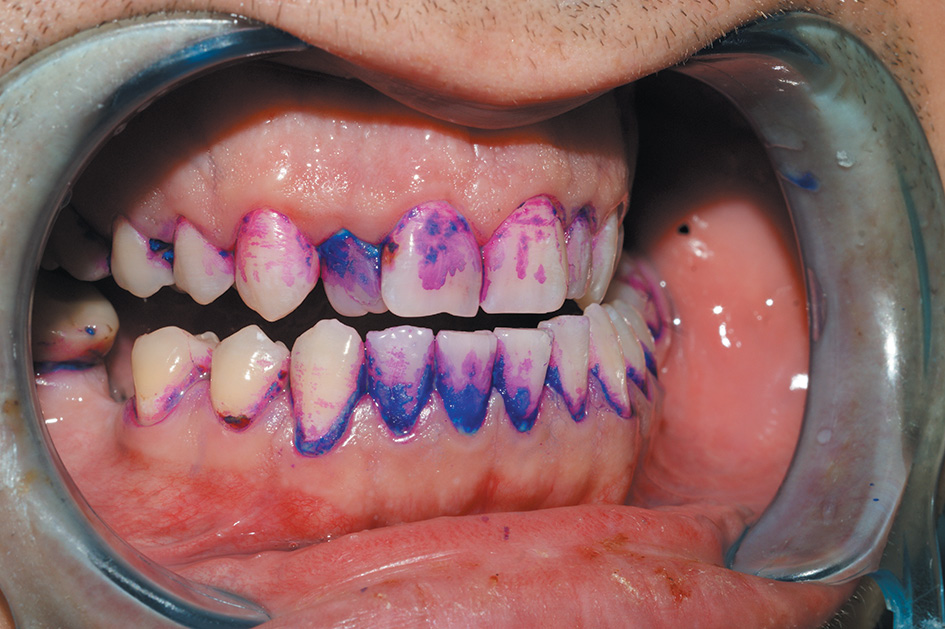

После проведенной гигиены в первой группе пациентов, даже при аккуратной и тщательной работе нейлоновыми щеточками, в 40 % случаев визуализировались остатки биопленки в местах скученности зубов, в труднодоступных участках, в 60 % случаев наблюдалось повреждение десны в пришеечной области. У всех пациентов второй группы после проведения профессиональной гигиены по протоколу GBT биопленка не визуализировалась, что подтверждает ее качественное удаление. Ключевым моментом для нас стало полное отсутствие повреждения маргинальной десны, сохранение ее целостности, что крайне важно у данной группы пациентов (рис. 2). Это связано с обработкой пришеечной зоны мелкодисперсным атравматичным порошком «Plus», который позволяет работать даже на мягких тканях, не повреждая их. Важной является возможность регулировки мощности подачи порошка в аппарате Prophylaxis Master: в придесневой области мы работали на значении мощности «2», по поверхности зуба использовали уровень мощности «6», «7» и более. Комфортной для пациентов является возможность подогрева струи воды до 40 °C при работе на аппарате Prophylaxis Master.

Рис. 2. Состояние тканей пародонта после профессиональной гигиены полости рта по протоколу GBT

Fig. 2. Periodontal tissue after the professional oral hygiene according to GBT protocol